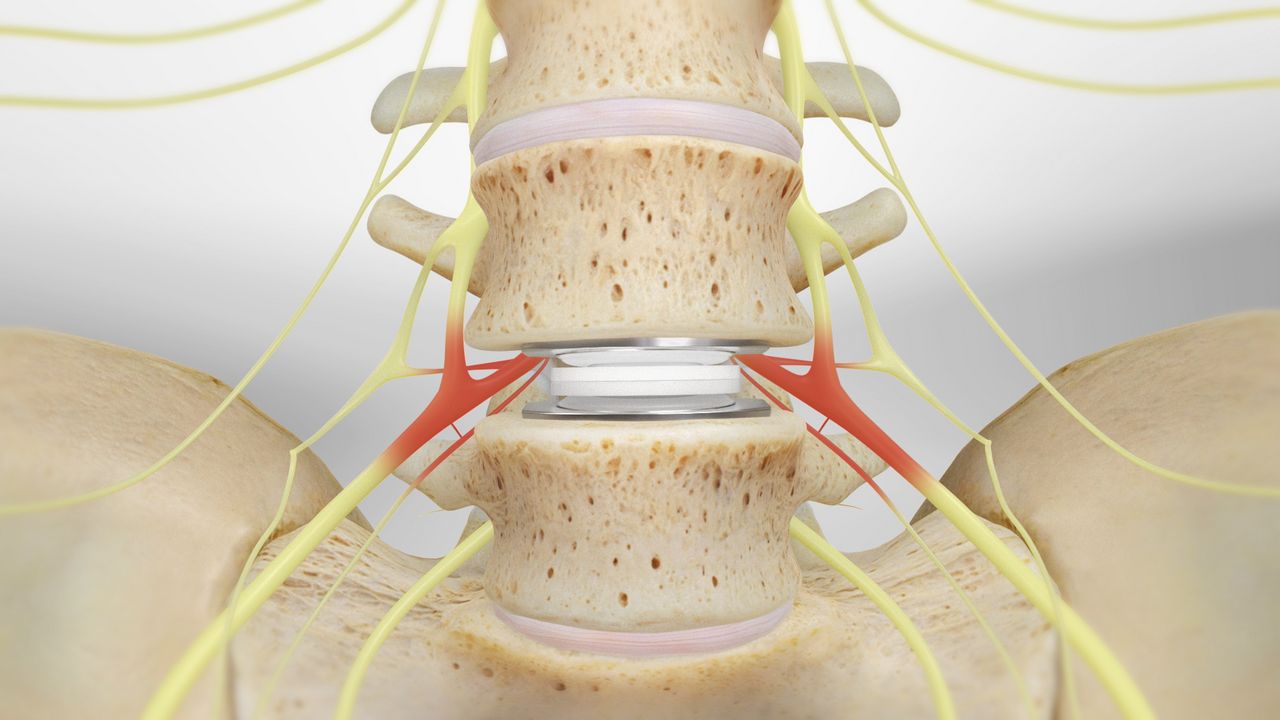

Hip fracture surgery is considered a very important procedure, as it can cause serious disruptions in the patient’s daily life. Imaging techniques are used to determine the location of the fracture before treatment. Conservative (non-surgical) treatment can be followed in cases of stable injuries, helping to reduce pain until recovery is achieved.

Hip fracture surgery may seem challenging, but it is considered a suitable treatment option for fractures in the hip area. The patient should see a doctor immediately to determine the appropriate treatment method and realign the fractured bones to their natural position. This can be done through either an incision in the hip area or by inserting screws or metal plates. Patients can typically leave the hospital after about two weeks, and complete recovery may take from 3 to 6 months.

Infections and wounds near the incision or injury site. Joint damage, as hip fractures can damage the cartilage surface of the joint. Injury to the sciatic nerve. If you would like to learn more about sciatic nerve injury and the development of sciatica, we recommend reading this article. The occurrence of something known as non-union, which is a rare problem. Anemia due to bone marrow damage. How Long Does Hip Fracture Recovery Take?

Hip fracture surgery can be scary for many people, and some may wonder if the bone returns to its normal state after the fracture. In reality, treating a hip fracture requires a surgical procedure, and the doctor may be able to realign the fractured bones after the break. This is done through a surgical procedure that involves proper fracture repair and stability of the bones using special plates. Therefore, hip fracture surgery should be performed under the supervision of a qualified surgeon after a comprehensive assessment of the case.